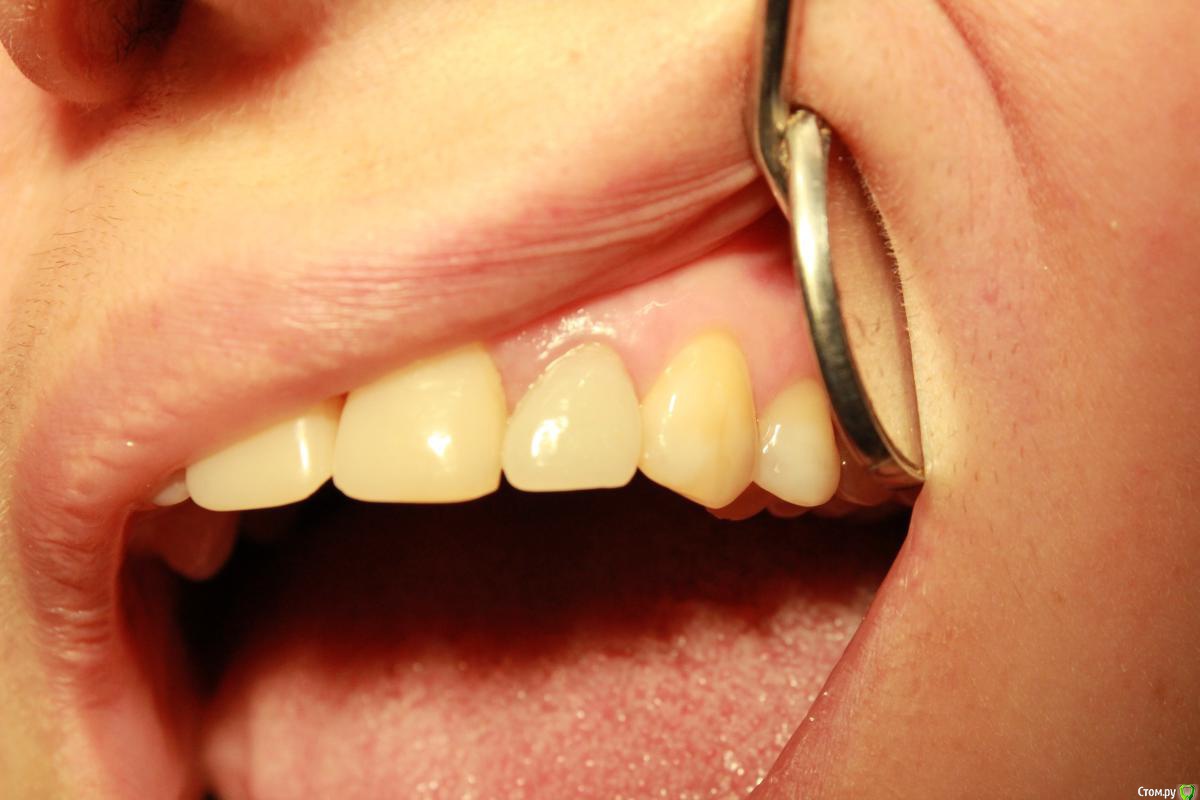

Sundance Опубликовано 9 июня, 2015 Поделиться Опубликовано 9 июня, 2015 Пациент категорически против удаления но пришлось временно удалить )))) и зафиксировать на мес. в новом положении через год с времянк ой 14 Ссылка на комментарий

Sundance Опубликовано 10 июня, 2015 Автор Поделиться Опубликовано 10 июня, 2015 Интересно конечно, но для чего это всё?пациент хотел спасти этот зуб))) робота имено в этом клиническом случаи експерементальная но в целом в аутотрансплантации результат 99% 1 Ссылка на комментарий